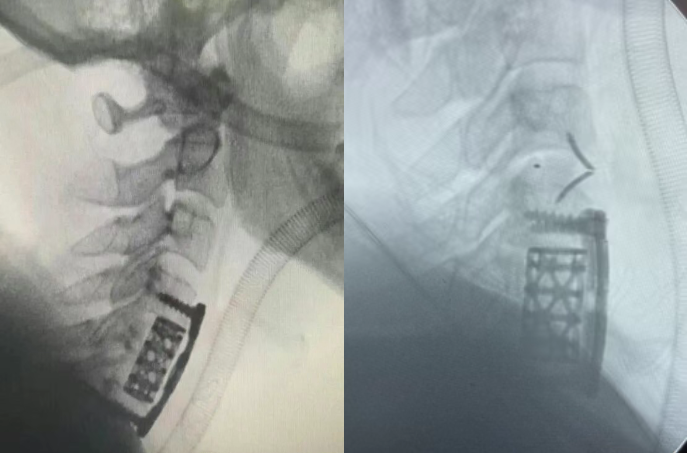

應(yīng)用效果展示:

ACCF術(shù)中需要切除病變椎體的大部分,僅保留椎體側(cè)方邊緣部分,術(shù)中還需要做頭端、尾端椎間盤的切除,減壓結(jié)束后取合適長(zhǎng)度的鈦網(wǎng)支撐(鈦網(wǎng)植入自體或異體骨粒),最后鈦板螺釘固定。

螺釘大擺角頸椎前路釘板系統(tǒng)ARIES-III型超薄板加上角度豐富規(guī)格齊全的鈦網(wǎng)及端蓋系統(tǒng)可以有效降低鈦網(wǎng)下沉情況,減少手術(shù)并發(fā)癥發(fā)生。